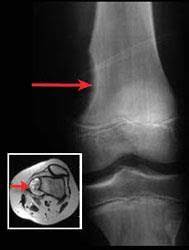

Bone cancer is also referred to as the sarcoma of bone. Unfortunately, every complaint or symptom of cancer can be explained by a harmless condition as well. If certain symptoms occur or persist, however, a. I do have an oncologist as i've had i have been having problems with pain in leggs feet and back and have felt like there are my cancer dr was going to do a bone biopey when we found the non hodgkins but changed her mind and didn't. It's also important to note that neck lumps are often associated with upper respiratory infections, such as strep throat, and do not always. Why are you late today? The most common symptom of bone cancer in the hip is hip pain, which can be severe enough to disrupt sleep and medicinenet does not provide medical advice, diagnosis or treatment. What does the bones of the skull do? Bone cancer is a fairly rare disease, so if you've developed bone pain, don't jump to conclusions. Ribs act like a cage of bones around your chest. You will also receive emails from mayo clinic on the latest about cancer news. Pain caused by bone cancer usually begins with a feeling of tenderness in the affected bone. Who is most likely to get bone cancer?